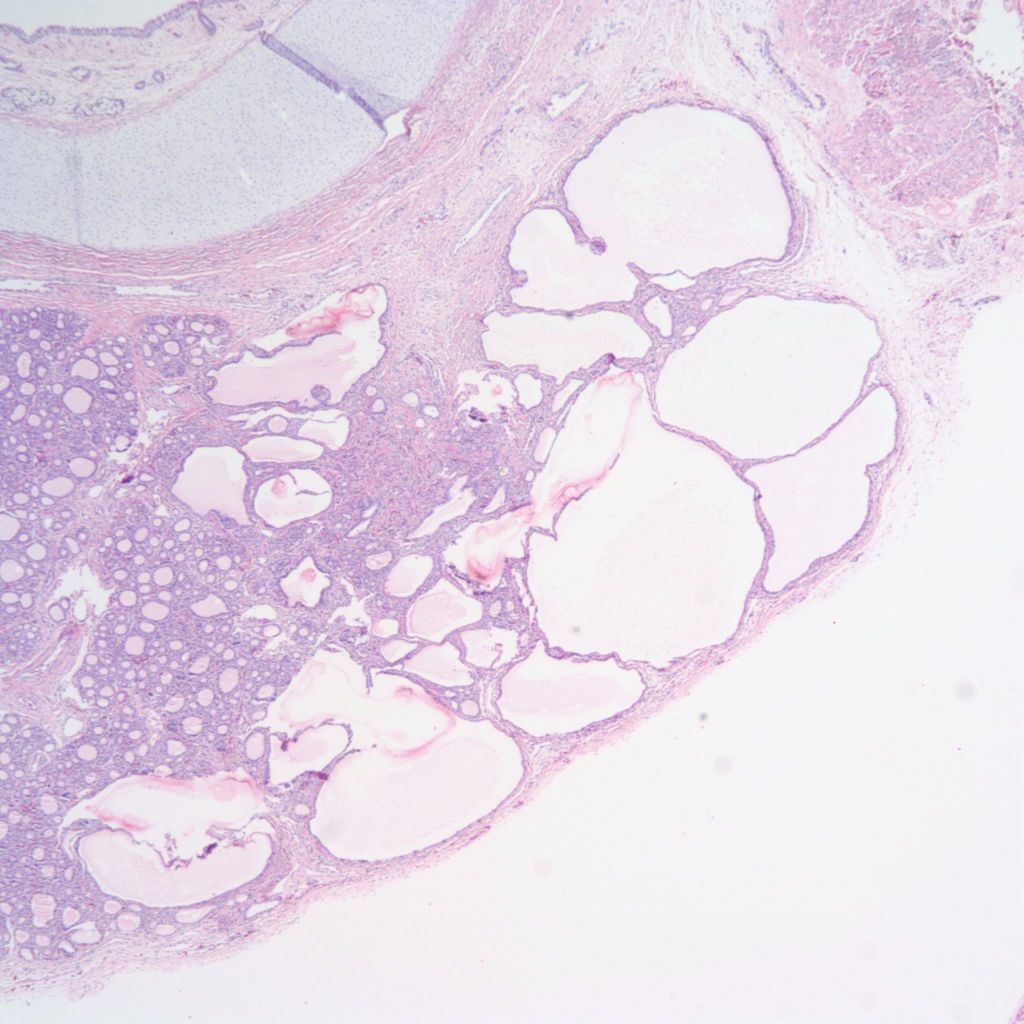

Other abnormalities: The thyroid can have focal clusters of enlarge follicles usually in the context of a maldevelopment syndrome including chromosomal trisomies. (Fig 6a, b).